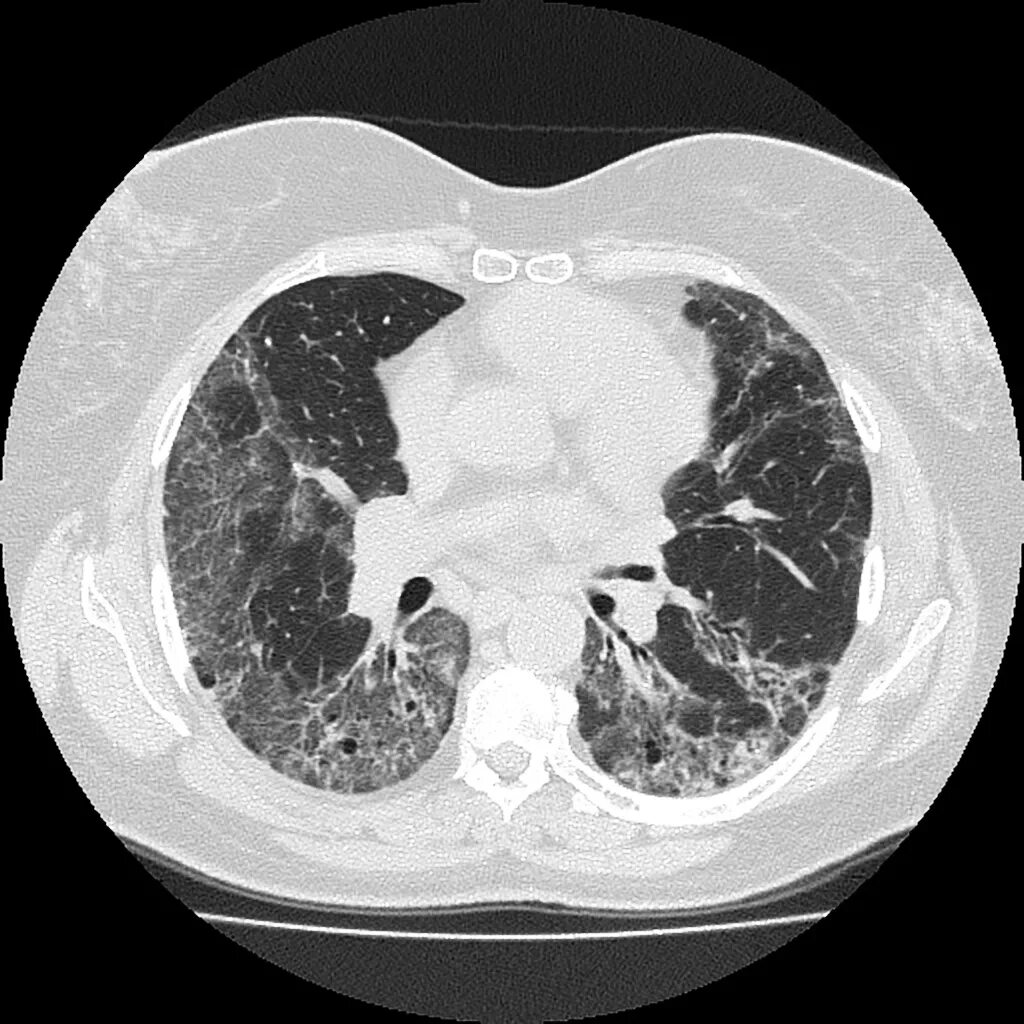

Non specific view